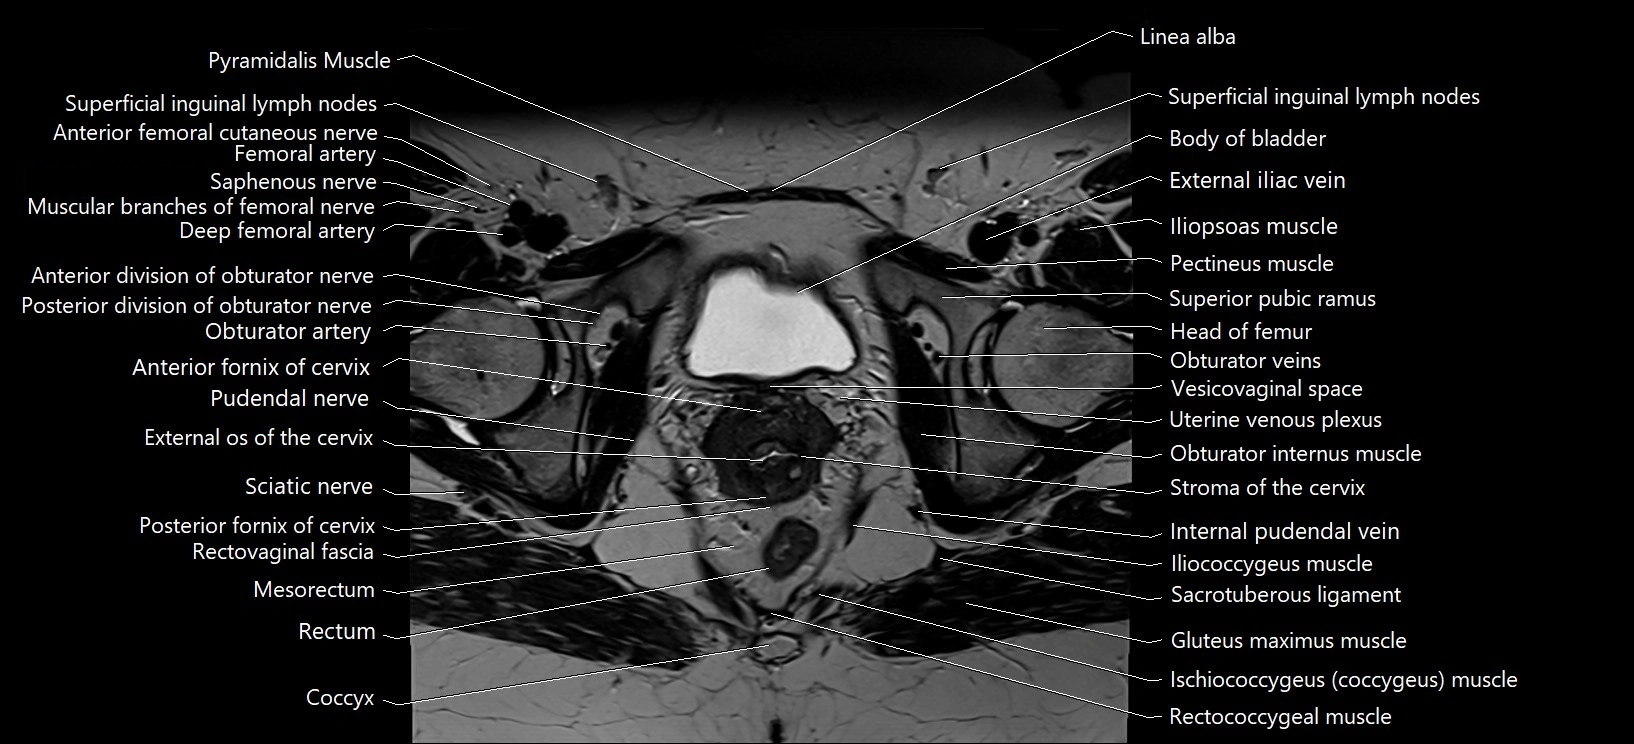

- Anterior fornix of cervix

- Body of urinary bladder

- Cervix of uterus

- Coccyx

- Common iliac vein

- External iliac vein

- External os of the cervix

- Iliococcygeus muscle

- Iliopsoas muscle

- Internal pudendal vein

- Linea alba

- Mesorectum

- Obturator internus muscle

- Obturator veins

- Posterior fornix of cervix

- Pudendal nerve

- Pyramidal muscle (pyramidalis muscle)

- Rectococcygeal muscle

- Rectovaginal septum (rectovaginal fascia)

- Rectum

- Sacrotuberous ligament

- Sciatic nerve

- Stroma of the cervix

- Superficial inguinal lymph nodes

- Uterine venous plexus

- Vesicovaginal space